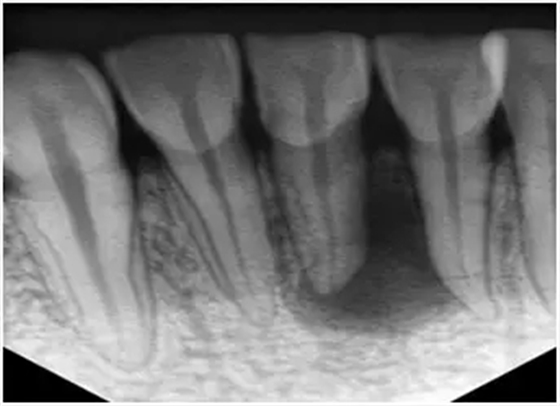

1、術(shù)前拍攝X線片

在根管治療過程中,在根管治療術(shù)前拍X線片,以幫助診斷,了解髓室的位置和根管數(shù)目及形態(tài),測量根管工作長度及日后隨訪和評價(jià)療效提供對比的依據(jù)。